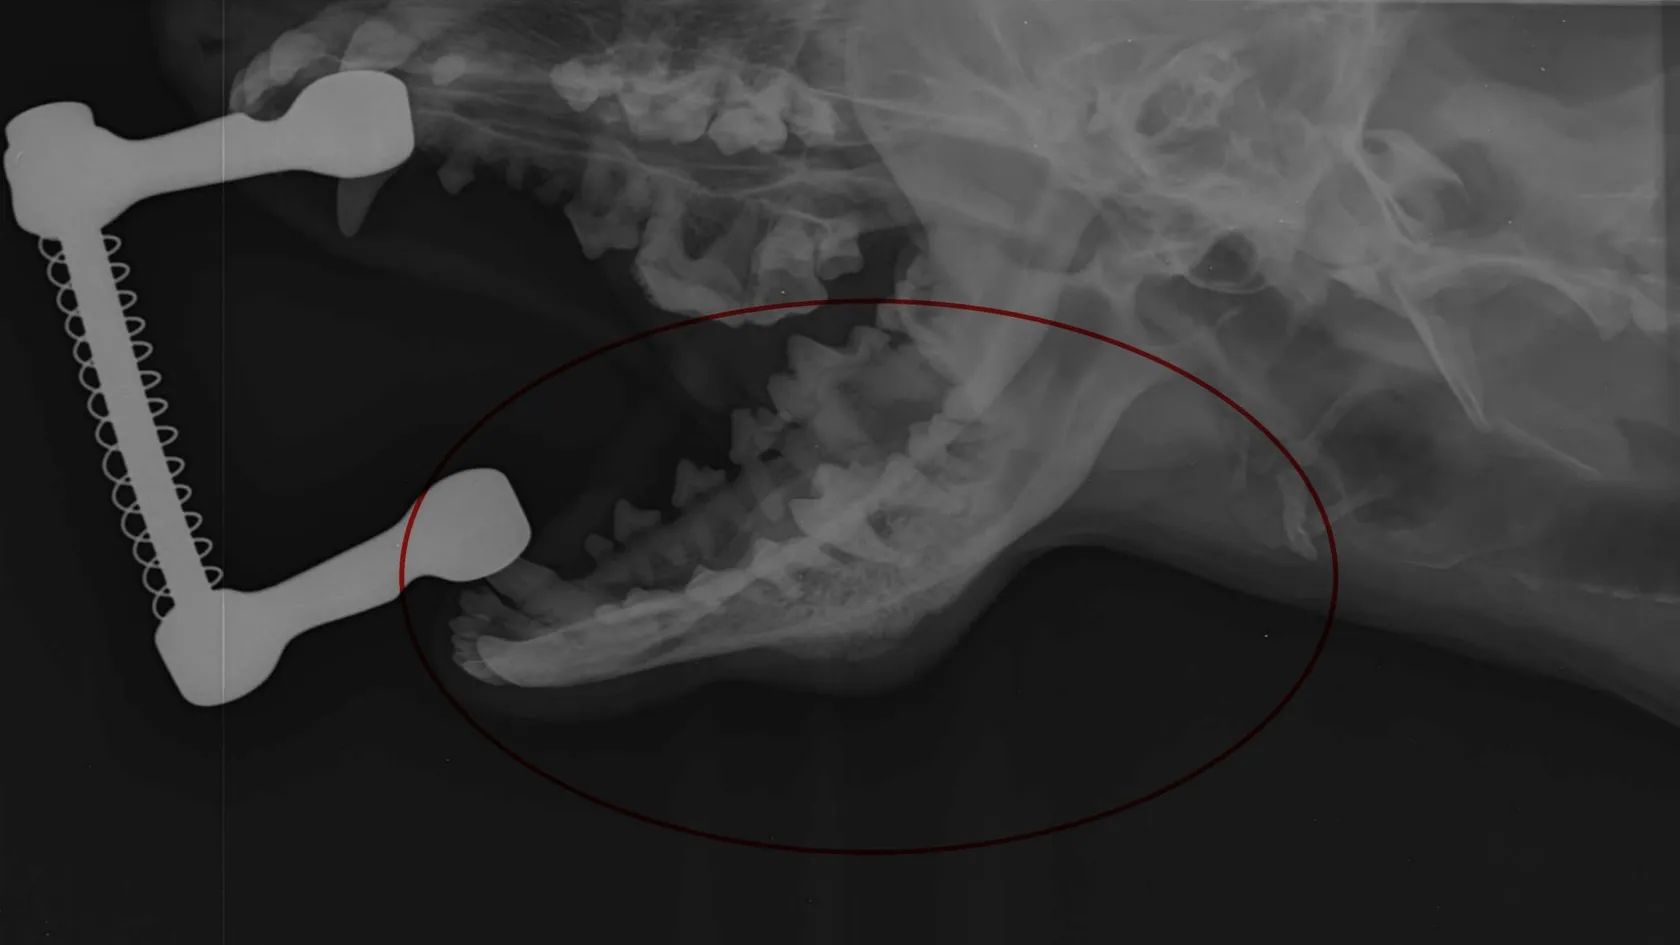

Provozuji půjčovnu elektrokol na jižní moravě www.jiznimoravanakole.cz a nabízím k prodeji zcela nové (zakoupeno 03/2026) elektrokolo CTM model Pulze GX velikosti rámu XL (20"), vhodné pro postavu 183 - 205 cm. Barva hlubokomodrá perleť. Elektrokolo je neježděné s nájezdem 0,7 km (pouze testovací jízda po sestavení a seřízení přehazovačky a brzd) viz. foto. Elektrokolo je vybaveno motorem Panasonic GX Power Plus s výkonem 75 Nm a baterií s kapacitou 720 Wh. Elektrokolo má čtyři stupně podpory s dojezdy na ECO 170 km, STD 124 km, AUTO 111 km a HIGH 97 km. Přehazovačka Shimano Cues 1 x 9 (11-46 zubů), hydraulické brzdy Shimano MT 200, pružinová vidlice Suntour se zdvihem 120 mm. Záruční list. DŮVOD PRODEJE NOVÉHO ELEKTROKOLA Z PŮJČOVNY ZA VÝHODNOU CENU: Elektrokolo bylo určeno ke každoročnímu omlazení flotily v mojí půjčovně elektrokol a doplnění početního stavu před začátkem nové sezóny. Bohužel můj 11-ti letý čtyřnohý parťák, pes ANDY, který mě provází při mojí práci a většina mých zákazníků se s ním setkala, trpí zhoubným nádorem čelisti a jeho paliativní léčba pomocí chemoterapie, která spomaluje růst nádoru v kosti je finančně hodně náročná.